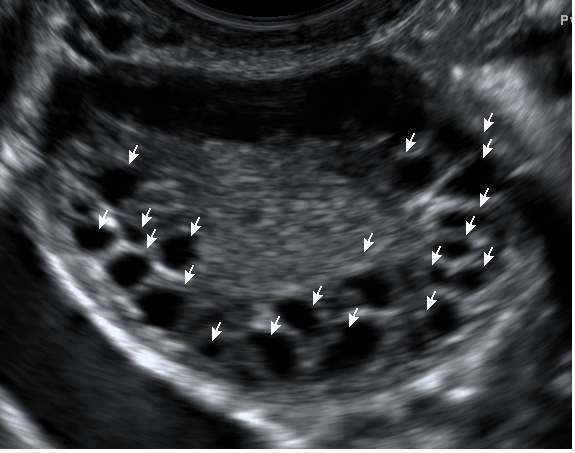

Созревание фолликула в яичнике: этапы и процессы